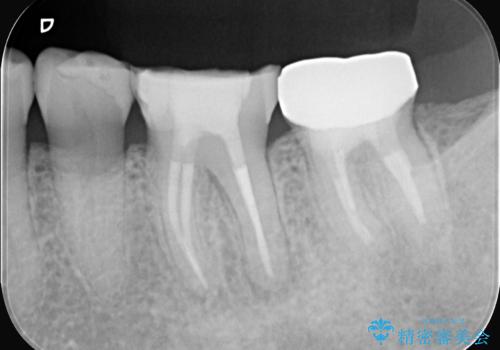

- 2日前から歯の痛みが続くという主訴でご来院されました。診察の結果、**不可逆性歯髄炎(歯の神経の重度の炎症)**と診断。レントゲンでは、歯髄腔が狭くなり、根管が石灰化している難症例であることが確認されました。患者様の大切な歯を残すため、歯科用顕微鏡を用いた精密根管治療を行うことで、狭く、見えにくい根管を正確に探し出し、治療を完了させる計画を立案しました。

今回の治療は、特に難易度の高い石灰化した根管が対象でした。まず、治療中の細菌感染を防ぐためにラバーダムを使用。次に、歯科用顕微鏡で治療部位を何十倍にも拡大しながら、狭窄した根管の入り口を探し、慎重に拡大・清掃を行いました。顕微鏡を用いることで、肉眼では不可能だった根管内部の細かい構造を確認しながら、感染源を徹底的に除去することができました。これにより、難症例の奥歯でも再発リスクを抑えた適切な処置を行うことができ、治療後に痛みは解消。大切な歯を長期間にわたり保存することができました。